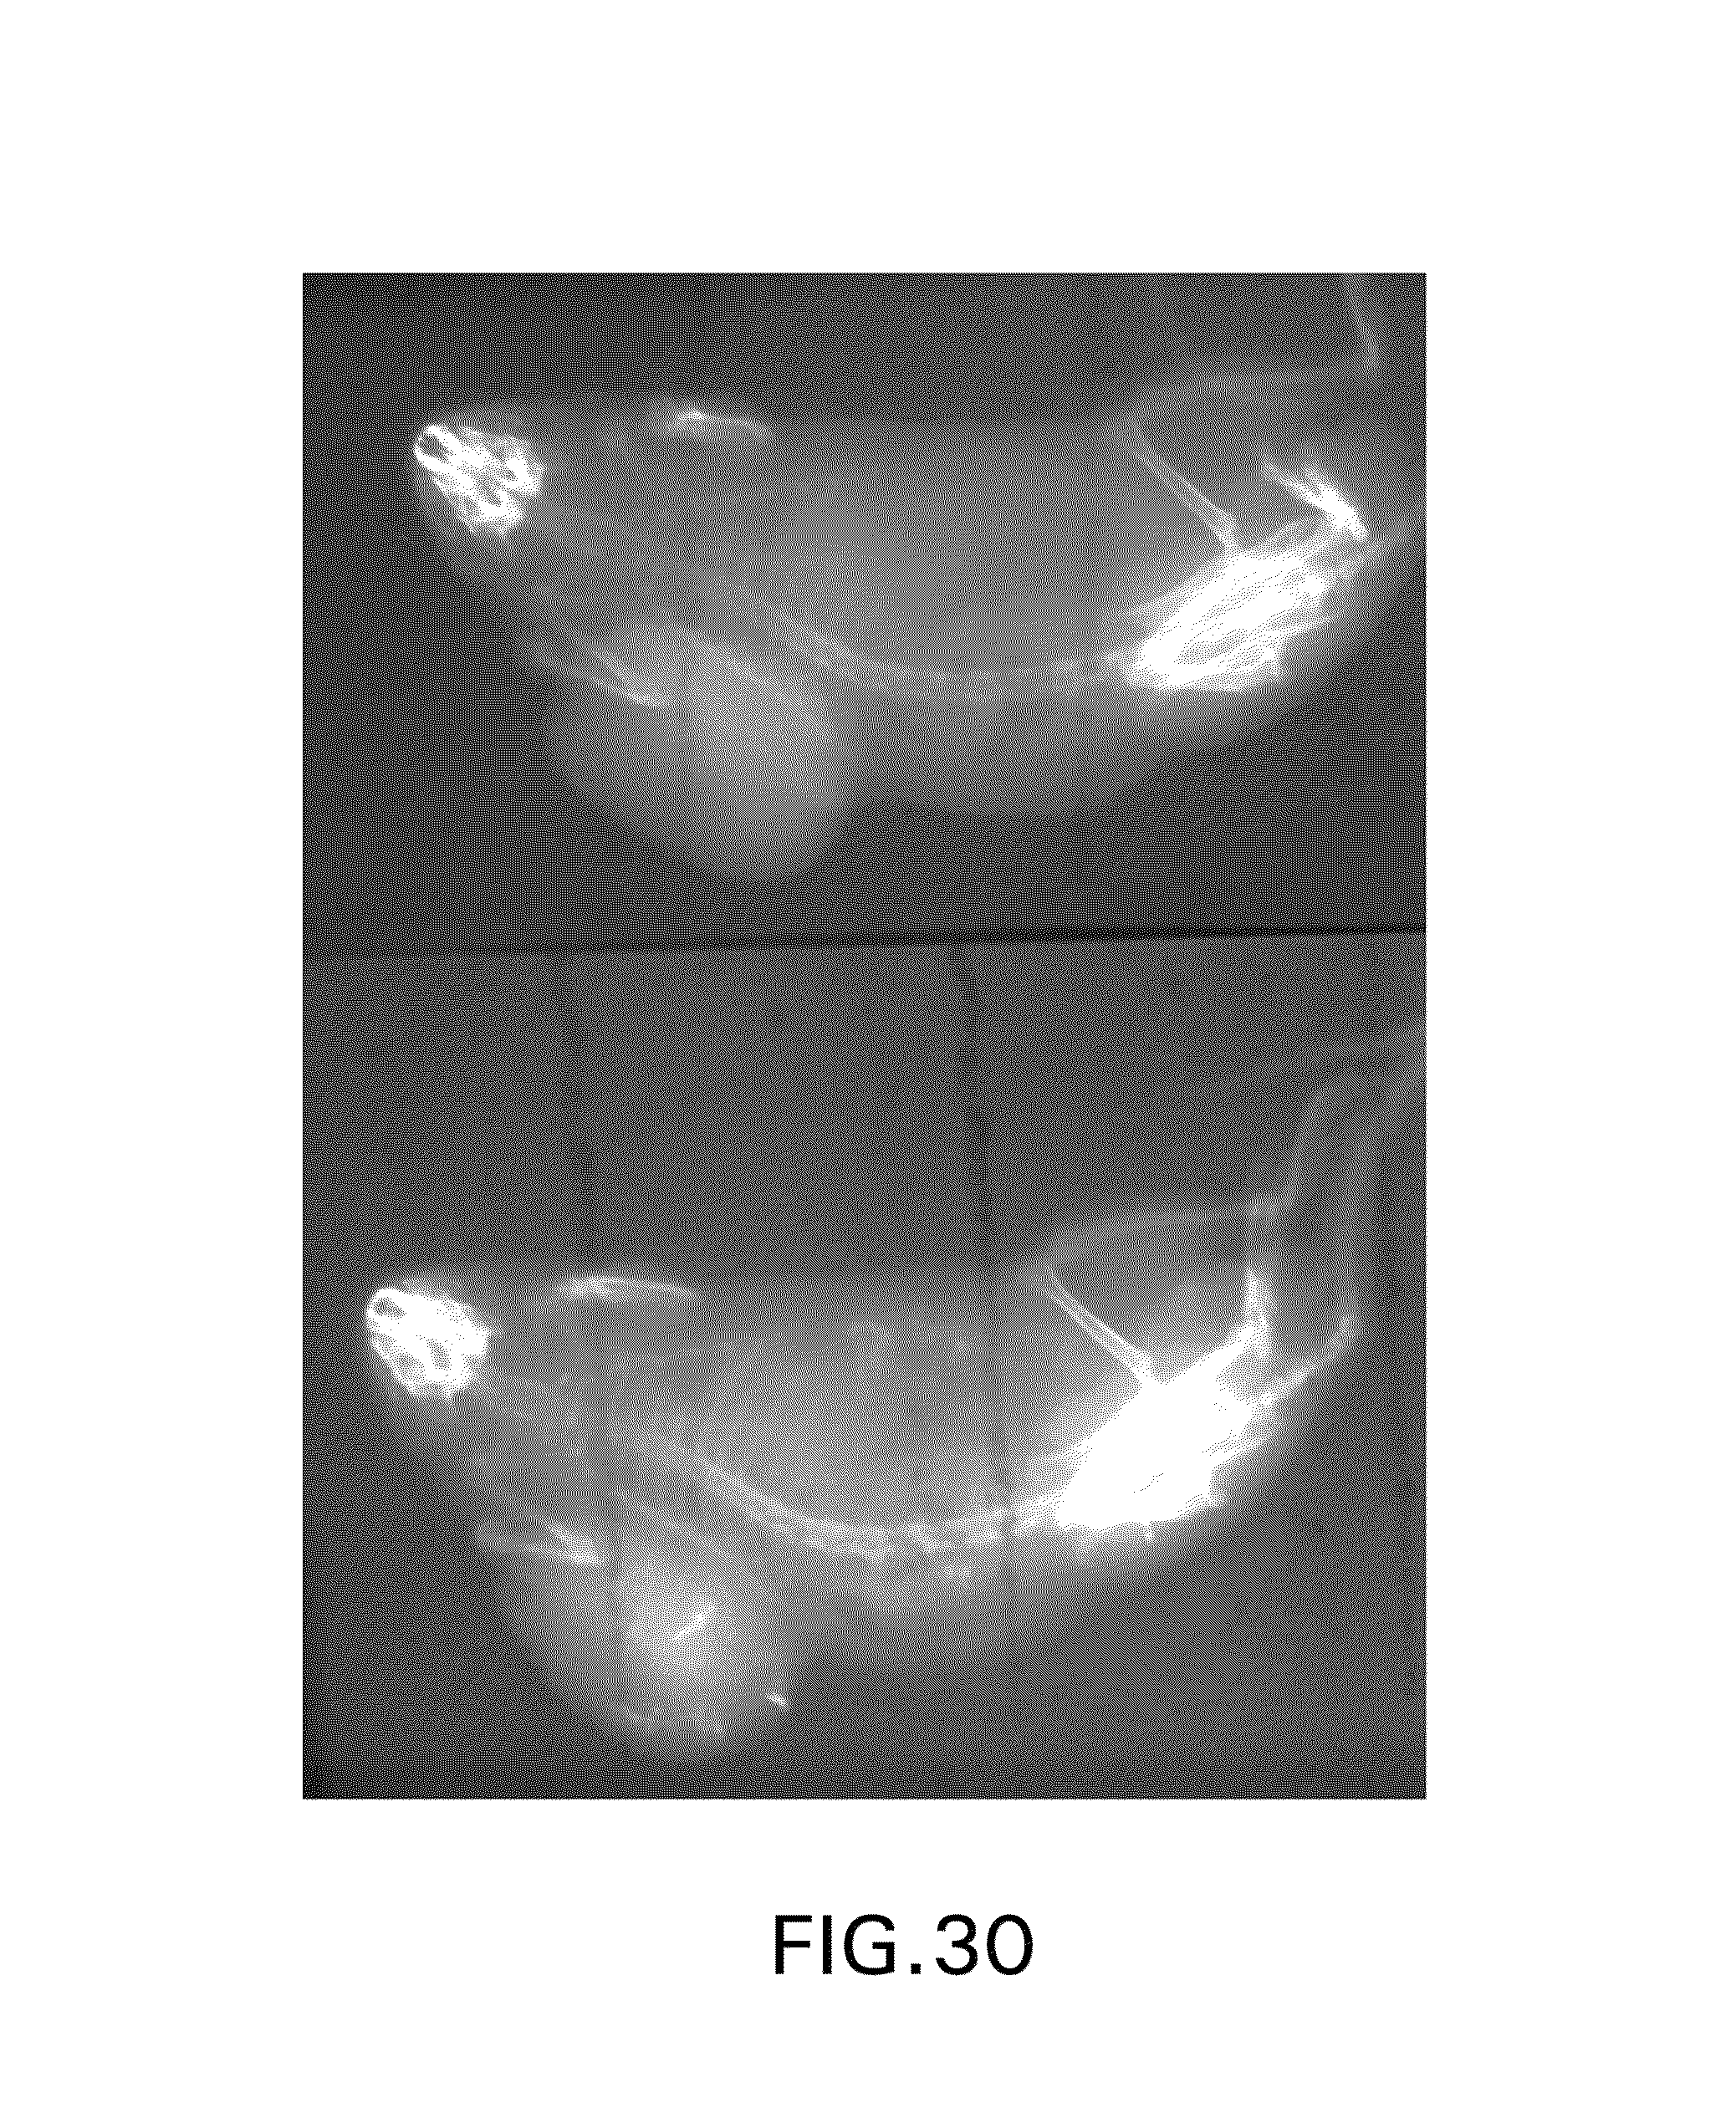

FIG. 30 is a pair of images showing radio-opaque sites of formation of an indigo-like product with an administered indigogenic compound, which are absent prior to administration of the indigogenic compound.